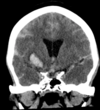

Based off of the imaging, what is the most likely diagnosis?

Epilepsy

Haemorrhage

Hydrocephalus

Normal

A